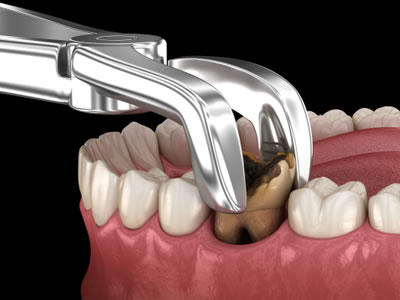

Tooth Extractions

It is the removal of a tooth from the mouth. Extractions are performed for wide variety of reasons, including tooth decay that has destroyed enough tooth structure to render the tooth non –restorable.